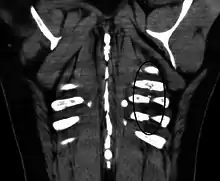

الكسر الضلعي هو كسر أو تحطم في واحد أو أكثر من العظام التي تشكل القفص الصدري. ونادراً ما يكسر الضلع الأول بسبب موقعه خلف عظم الترقوة والذي يجعله محمياً . ومع ذلك، إذا ما تم كسرها، يمكن أن تحدث أضراراً جسيمة في الضفيرة العضدية من الأعصاب والأوعية تحت الترقوة. الكسور في الضلعين الأول والثاني غالباً ما تكون مرتبطة مع إصابات في الرأس والوجه أكثر من ارتباطها بكسور في الأضلاع الأخرى. كسور الضلوع الوسطى هي الأكثر شيوعاً.[1] الكسور عادة ما تحدث من ضربات مباشرة أو غير مباشرة من إصابات السحق. أضعف جزء من الضلع هو فقط المنطقة الأمامية لزاويته، ولكن يمكن أن يحدث الكسر في أي مكان. الأضلاع الأكثر تعرضاً للكسر هي الضلع السابع والضلع العاشر. الكسور في الأضلاع السفلية قد تؤدي لمضاعفات محتملة كإصابة الحجاب الحاجز، والذي ينتج عنها فتق الحجاب الحاجز.[2] كسور الأضلاع غالباً ما تكون مؤلمة جداً لأن الأضلاع يجب أن تتحرك للسماح للتنفس. عندما يتم كسر العديد من الأضلاع في عدة أماكن ينتج عن ذلك صدر سائب، وتتحرك أجزاء العظم المنفصلة بصورة منفصلة عن باقي الصدر.

معرض صور